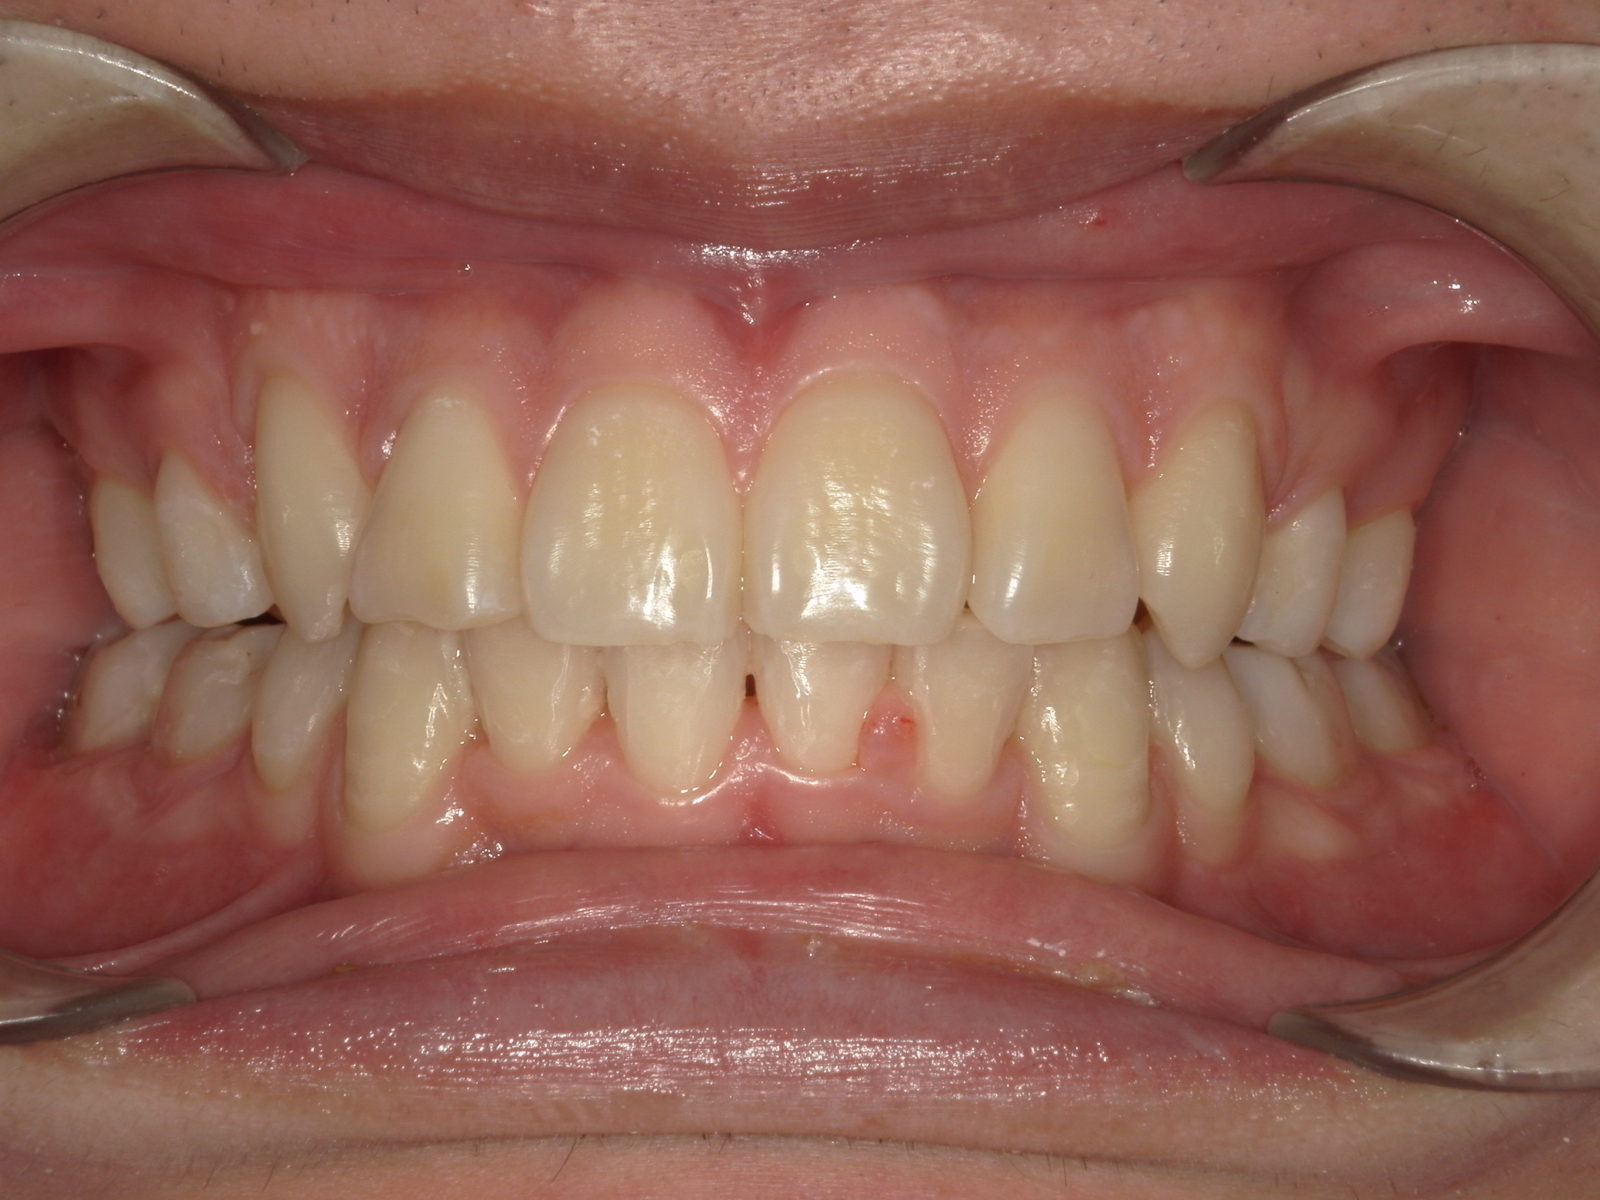

【主訴】出っ歯が気になる

【診断結果】上顎前突

【治療開始時の年齢】18歳

【治療内容】マウスピース型 (カスタムメイド) 矯正装置

【抜歯部位】上下左右4番目

【治療経過】後戻り無

【治療期間】1年8ヶ月

【治療費用】882,200円

【リスク・副作用】

治療初期の段階では痛みや不快感が生じる可能性がある。適切に歯磨きをしないと虫歯になる可能性が高くなる。個人差により予想された治療期間より長くなる場合がある。治療後はリテーナーを装着しないと後戻りしてしまうリスクがある。